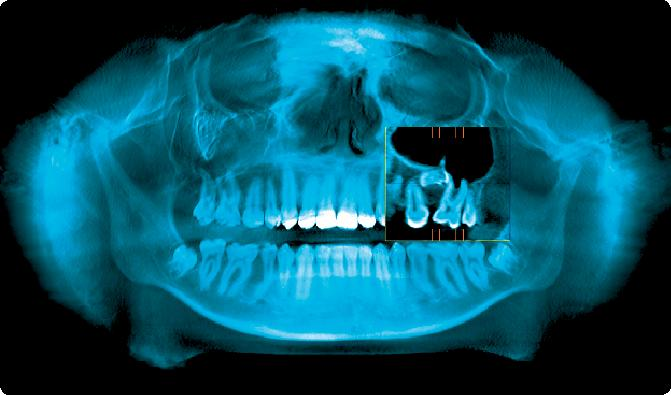

The i-CAT® Cone Beam 3-D Dental Imaging System allows Dr. Reid to analyze the anatomy of his patient's mouth, face, and jaw areas by producing complete three-dimensional views of these oral and facial structures. This then leads to more accurate treatment planning and predictable outcomes for needed surgical procedures.

The i-CAT® plays an important role in diagnosis and treatment planning, as well as providing accurately assessed tooth relationships and relative anatomy for orthodontic treatment. Not only does it expose patients to less radiation than regular CT scans do, it also makes 3-D imaging quicker, easier, and much more cost effective.

From the initial diagnosis, through planning and treatment, to successful case completion, the i-CAT® provides Dr. Reid with the flexibility to select specifically desired scans in order to manage radiation dose control. Using this system, he can optimize orthodontic treatment plans, map surgical treatment plans, and place and restore implants with greater accuracy and confidence. This reduces surgery and anesthesia time, which translates into smoother recoveries for patients.